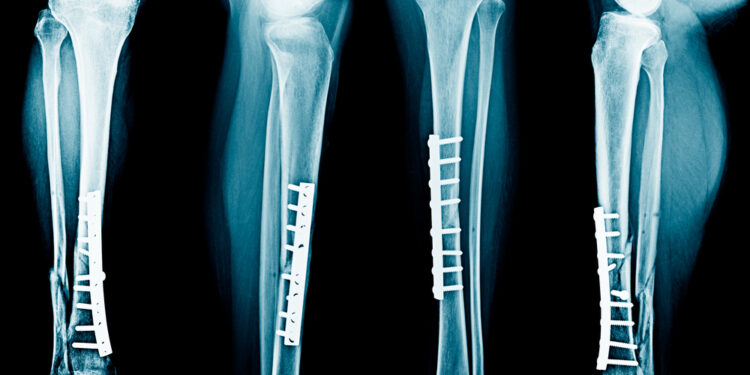

- Vidinė fiksacija – operacijos metu kaulai sutvirtinami specialiomis plokštelėmis, vinimis ar sraigtais